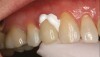

(4.) Single maxillary lithium disilicate crown.

Figure 4

(5.) Crown placed using bioceramic cement (buccal and occlusal views).

Figure 5

(6.) Crown placed using bioceramic cement (buccal and occlusal views).

Figure 6